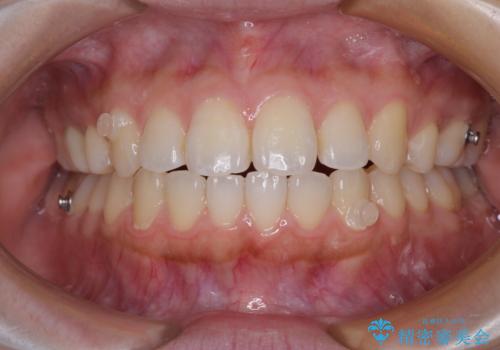

再矯正 開咬に後戻りした歯列をインビザラインで改善

- 矯正治療の後戻りを気にして来院された患者様です。

デコボコと上下前歯の隙間が気になるものの、しっかりと治療をしたいという意思はないとのことで、インビザラインの中でもアライナー数に制約のあるライトパッケージを用いて、治療できる範囲まで歯列を改善していくこととしました。

インビザラインは前歯部の開咬に効果的であることが多く、ライトパッケージにもかかわらず、十分満足のいく仕上がりとなりました。